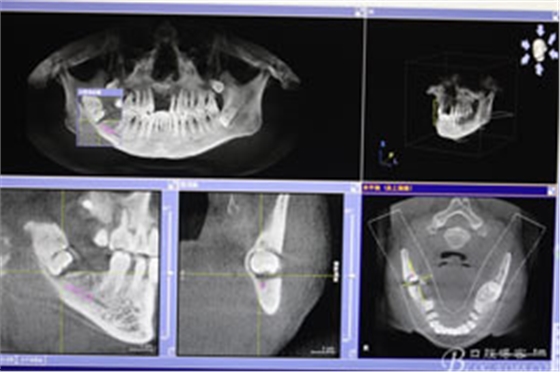

圖4.總體的CBCT影像: